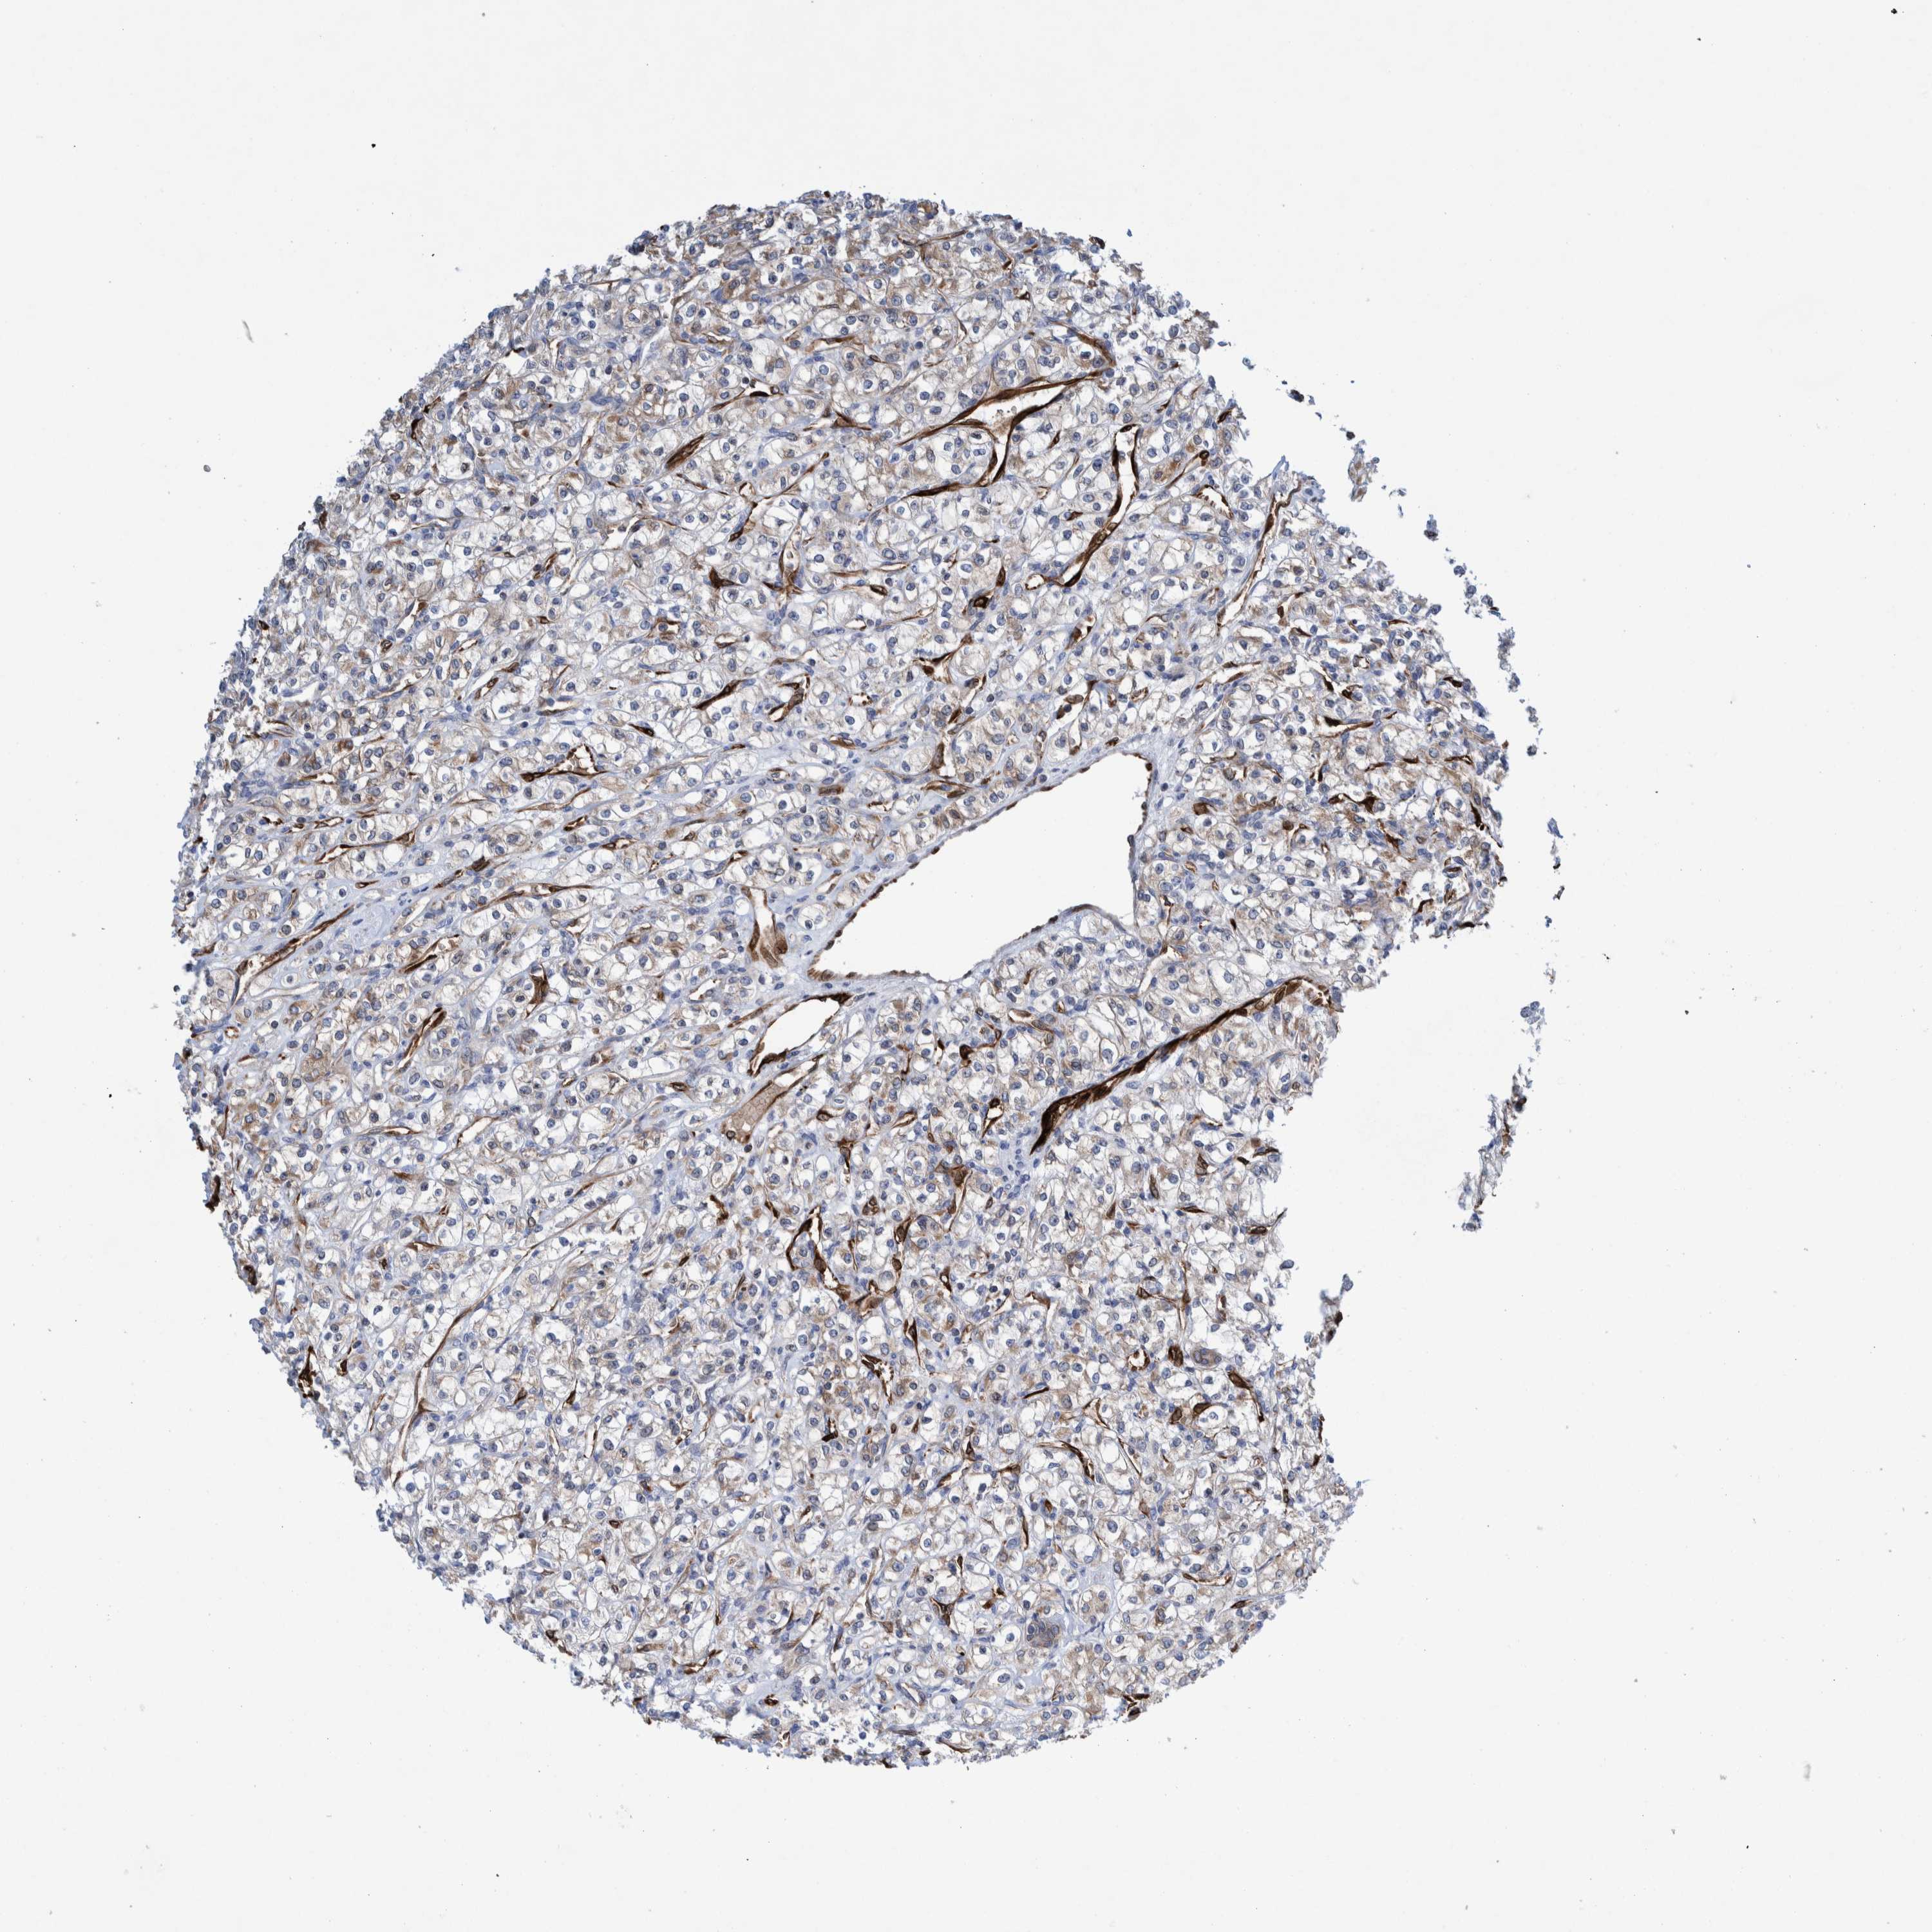

KIDNEY RENAL CLEAR CELL CARCINOMA (TCGA) - Interactive survival scatter ploti

The Survival Scatter plot shows the clinical status (i.e. dead or alive) for all individuals in the patient cohort, based on the same data that underlies the corresponding Kaplan-Meier plots. Patients that are alive at last time for follow-up are shown in blue and patients who have died during the study are shown in red.

The x-axis shows the expression levels (FPKM) of the investigated gene in the tumor tissue at the time of diagnosis. The y-axis shows the follow-up time after diagnosis (years). Both axes are complimented with kernel density curves demonstrating the data density over the axes. The top density plot shows the expression levels (FPKM) distribution among dead (red) and alive patients (blue). The right density plot shows the data density of the survived years of dead patients with high and low expression levels respectively, stratified using the cutoff indicated by the vertical dashed line through the Survival Scatter plot. This cutoff is automatically defined based on the FPKM cutoff that minimizes the p-score. The cutoff can be changed by dragging the vertical line or by entering a cutoff value in the square labeled "Current cut-off".

Under the Survival Scatter plot the p-score landscape (black curve; left axis) is shown together with dead median separation (red curve; right axis). Dead median separation is the difference in median mRNA expression between patients who have died with high and low expression, respectively. It is calculated as follows: median FPKM expression of dead patients with high expression - median FPKM expression of dead patients with low expression. This is intended to aid the user in visually exploring custom cutoffs and the associated p-scores and dead median separation.

Individual patient data is displayed and can be filtered by clicking on one or more of the category buttons on the top of the page. Categories describing expression level and patient information include: high, low, alive, dead, female, male and tumor stages. The scale of the x-axis can be toggled between linear and log-scale by clicking on the "x log" button. Mouse-over function shows TCGA ID, patient information and mRNA expression (FPKM) for each patient.

& Survival analysisi

Kaplan-Meier plots summarize results from analysis of correlation between mRNA expression level and patient survival. Patients were divided based on level of expression into one of the two groups "low" (under cut off) or "high" (over cut off). X-axis shows time for survival (years) and y-axis shows the probability of survival, where 1.0 corresponds to 100 percent.

THEM6 is potential prognostic, high expression is favorable in Kidney Renal Clear Cell Carcinoma (TCGA)

Best expression cut offi

Based on the FPKM value of each gene, patients were classified into two groups and association between prognosis (survival) and gene expression (FPKM) was examined. The best expression cut-off refers the FPKM value that yields maximal difference with regard to survival between the two groups at the lowest log-rank P-value. Best expression cut-off was selected based on survival analysis .

When clicking on this number, the vertical dashed line indicating cut-off, the interactive survival plot, and the Kaplan-Meier curve will be adjusted to show results based on the best expression cut-off.

: 17.02

TCGA RNA samplesi

RNA-seq data is reported as average FPKM (number Fragments Per Kilobase of exon per Million reads), generated by the The Cancer Genome Atlas (TCGA) .

Normal distribution across the dataset is visualized with box plots, shown as median and 25th and 75th percentiles. Points are displayed as outliers if they are above or below 1.5 times the interquartile range. FPKM values of the individual samples are presented next to the box plot.

Average pTPM 24.2

Number of samples 521